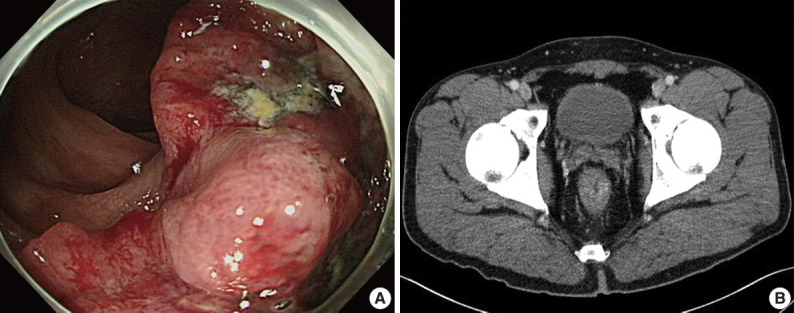

BRCA genes have well-known associations with breast and ovarian cancers. However, variations in the BRCA gene, especially germline variations, have also been reported in colorectal cancer (CRC). We present the case of a rectal cancer with a germline BRCA1 variation inherited from the paternal side. A 39-year-old male was admitted with rectal cancer. The patient underwent surgical resection and the pathologic diagnosis was adenocarcinoma. Next-generation sequencing was performed and a BRCA1 variant was detected. Reviewing the public database and considering the young age of the patient, the variant was suggested to be germline. The patient's father had had prostate cancer and next-generation sequencing testing revealed an identical BRCA1 variant. In the BRCA cancer group, there is relatively little attention paid to male cancers. The accumulation of male CRC cases linked to BRCA variations may help clarify the potential pathological relationship between the two.